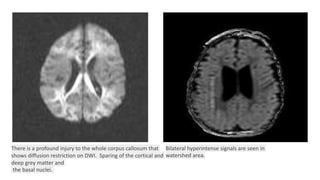

There is a profound injury to the whole corpus callosum that

shows diffusion restriction on DWI. Sparing of the cortical and

deep grey matter and

the basal nuclei.

Bilateral hyperintense signals are seen in

watershed area.

There is aprofound injury to the whole corpus callosum that shows diffusion restriction on DWI. Sparing of the cortical and deep grey matter and the basal nuclei. Bilateral hyperintense signals are seen in watershed area.